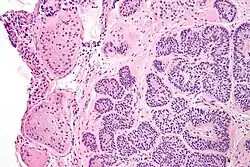

| Micrograph of a Sertoli cell nodule. H&E stain. | |

A Sertoli cell nodule is a benign proliferation of Sertoli cells that arises in association with cryptorchidism (undescended testis).[1] They are not composed of a clonal cell population, i.e. neoplastic; thus, technically, they should not be called an adenoma.[2]

Sertoli cell nodules are unencapsulated nodules that consist of:[2][3][4]

- cells arranged in well-formed tubules (that vaguely resemble immature Sertoli cells), with

- bland hyperchromatic oval/round nuclei that are stratified, and

- may contain eosinophilic (hyaline) blob in lumen (centre).

Micrograph of a Sertoli cell nodule. H&E stain.

Micrograph of a Sertoli cell nodule. H&E stain. -

Micrograph of a Sertoli cell nodule. H&E stain.

Micrograph of a Sertoli cell nodule. H&E stain.